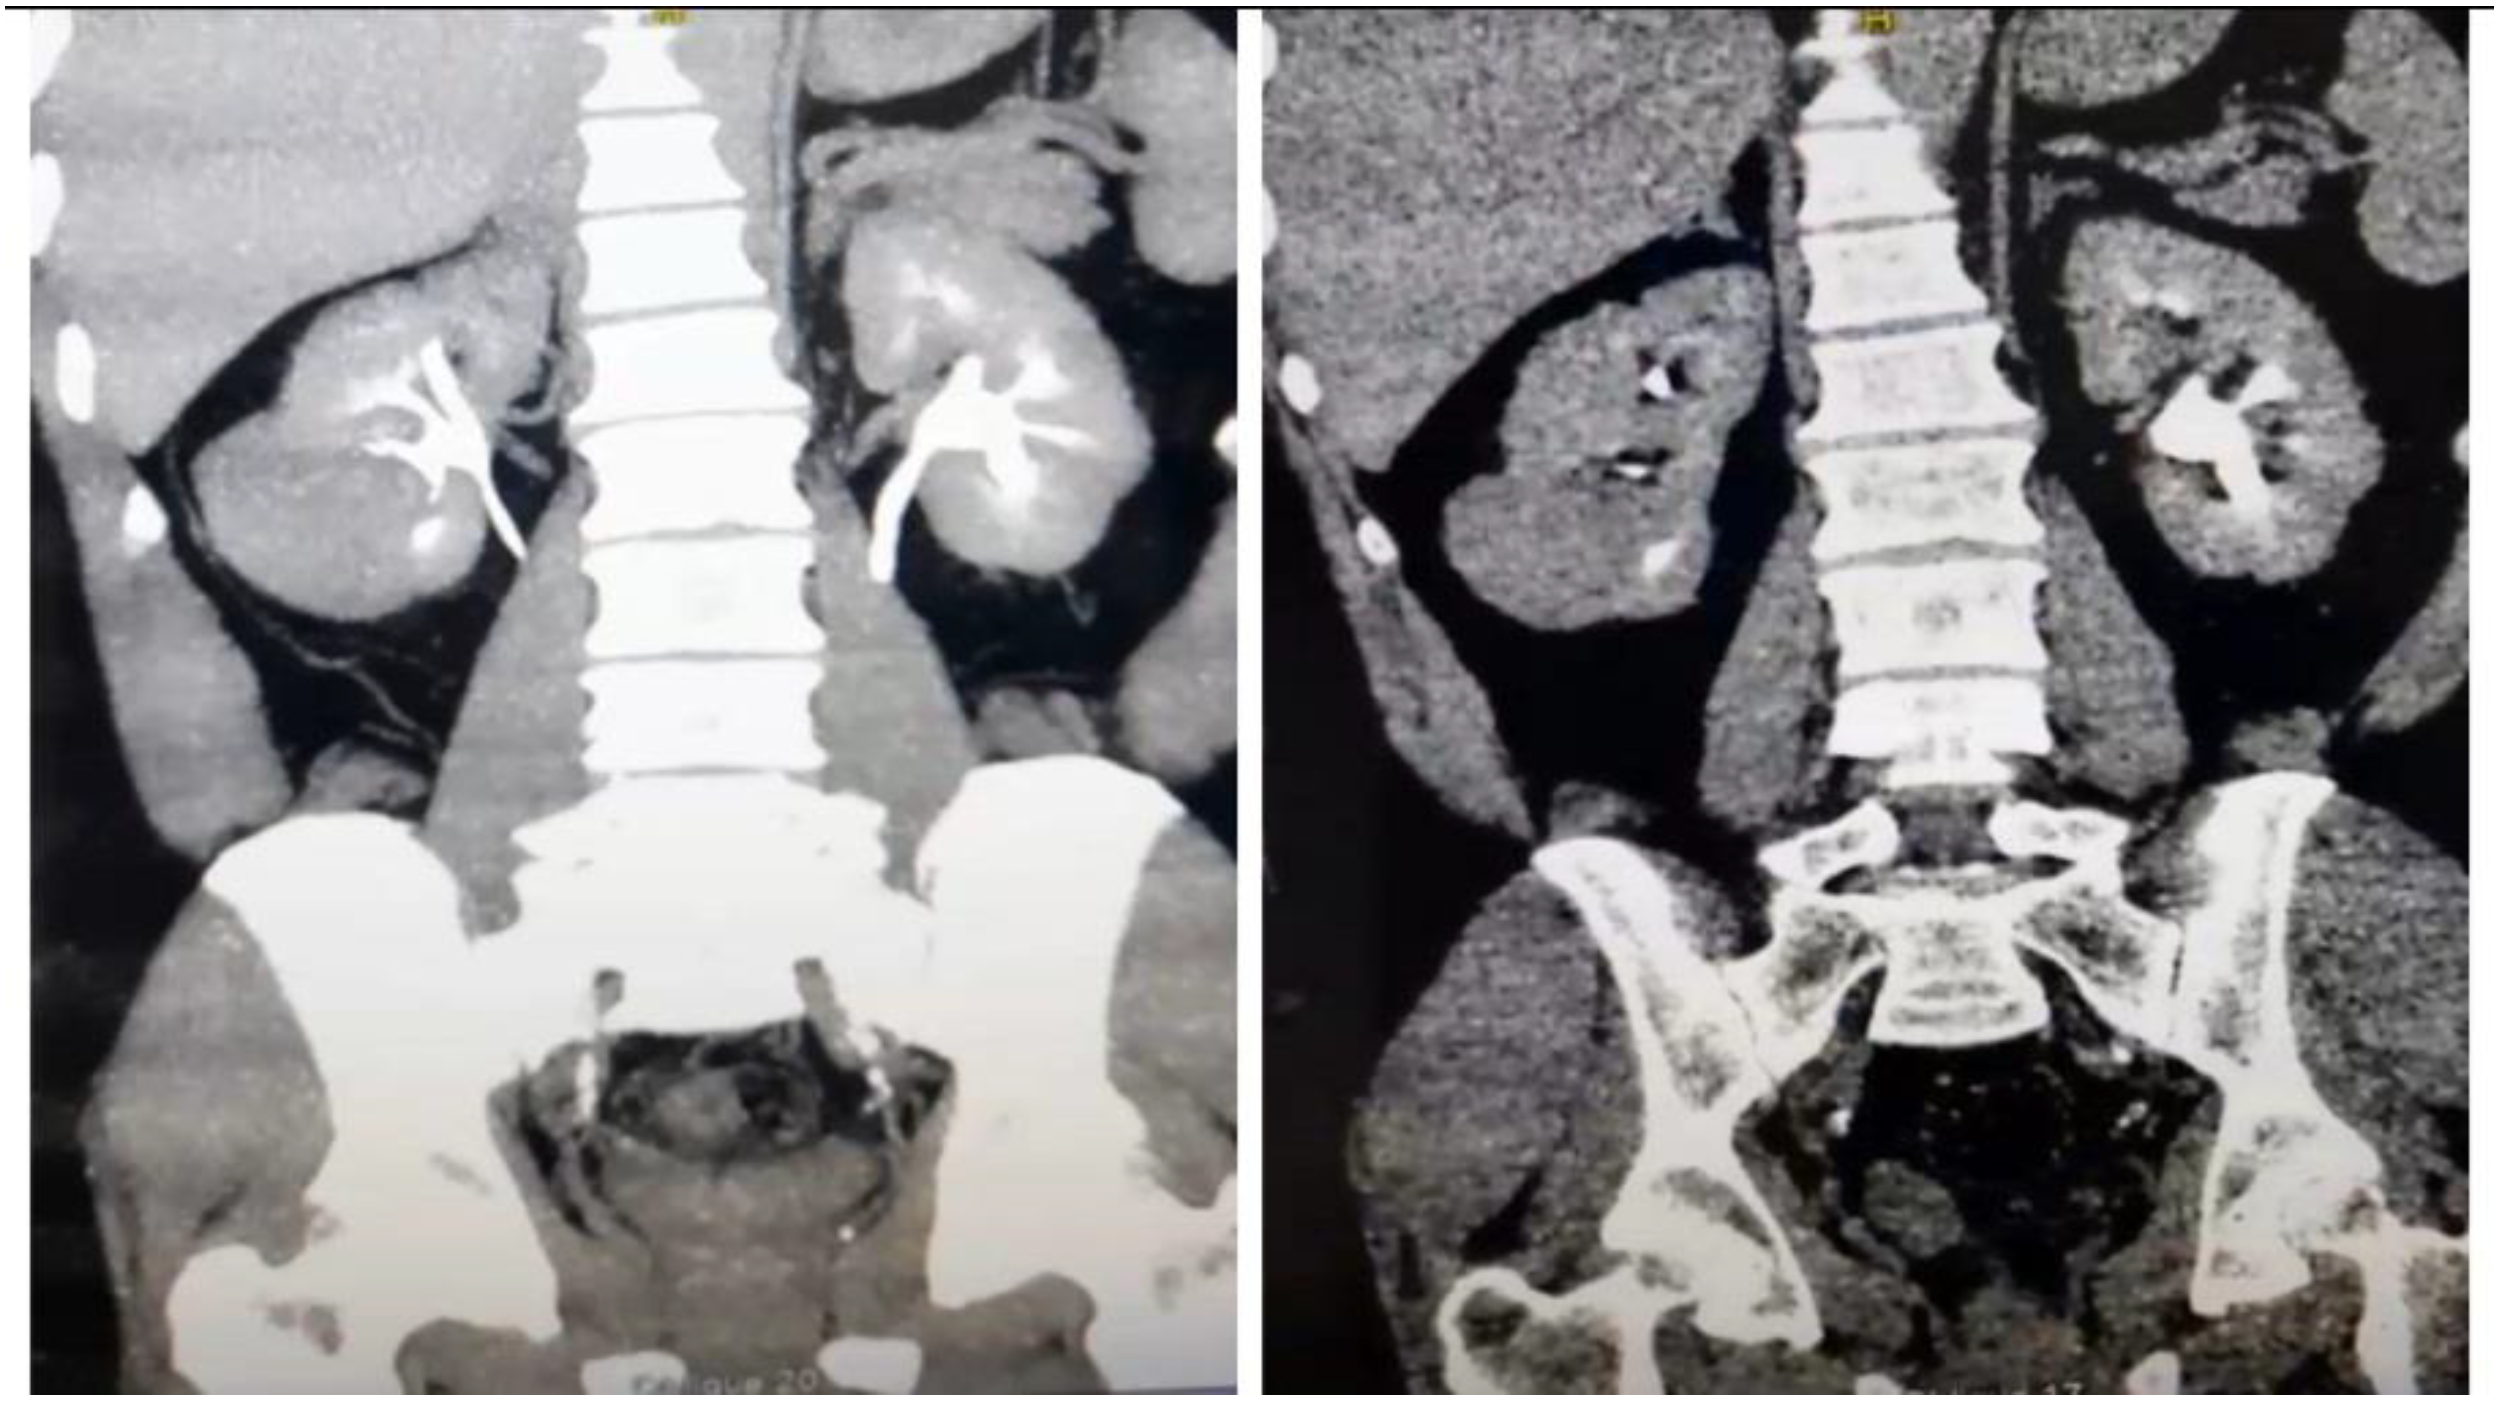

Radiograph of the left arm revealed a pathological humerus fracture (Figure 1).

Figure 1. X-ray of left arm.